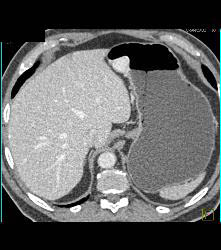

Glomus Tumor